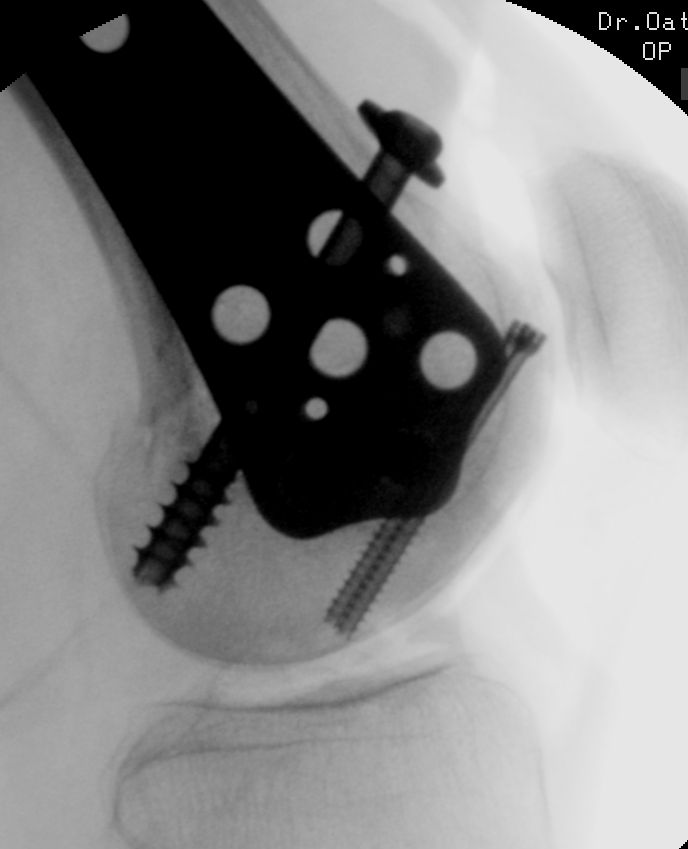

I love it when you step back to look at the imaging following an case - and the result ends up being some utterly minimalistic yet biomechanically elegant solution.

Every single screw has a single simple purpose, yet the big picture is a construct which locks together

#orthosky #orthopedics

December 4, 2024 at 5:20 PM